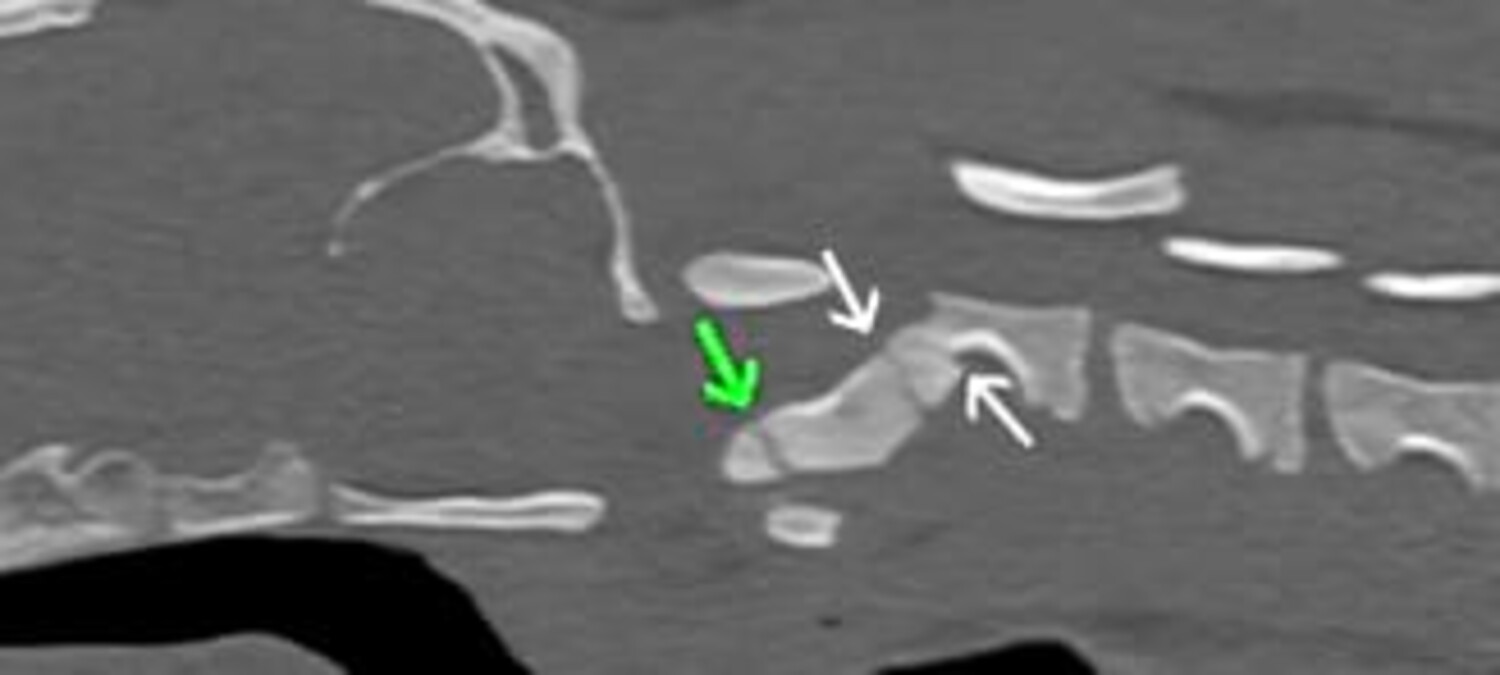

CT-Befund

• Es zeigten sich bilaterale, lineare, hypoattenuierende Linien durch die dorsalen Bögen (Laminae) von C1 (Atlas), was auf Frakturen hindeutet.

• Es besteht eine kraniale Verlagerung des Dens axis (Odontoidfortsatz) in Richtung des Foramen vertebrale von C1, was auf eine atlantoaxiale Subluxation bzw. Instabilität hinweist.

• Der Dens selbst ist nicht frakturiert, aber malpositioniert.

• Die Wachstumsfugen sind noch offen, was bei einem Welpen normal ist.

• Es zeigt sich eine Abflachung des ventralen Spinalkanals auf Höhe des Dens, was auf eine Einengung (Stenose) und mögliche Rückenmarkskompression hindeutet.

• An den Wirbelkörpern von C2 sind zwei frische Frakturlinien sichtbar, die auf akute Frakturen hinweisen, mit einer mittleren Frakturverschiebung (Verhältnis 1,39), was auf eine mittelstarke bis starke Verrenkung schließen lässt.

Abb. 2: CT – Frakturlinien mit weißen Pfeilen, Wachstumsfuge mit grünem Pfeil gekennzeichnet